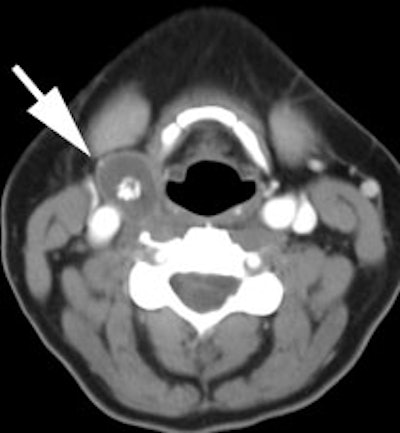

| Recurrent thyroid carcinoma and a negative PET scan: The patient shown below had a history of thyroid cancer and presented with an elevated thyroglobulin level. On a diagnostic CT scan, the patient was found to have a cystic lesion in the right upper neck containing a central calcification. A whole body I-131 scan was negative and a subsequent PET scan was performed. The PET scan demonstrated no tracer uptake within the patients cystic right neck mass. At surgery, the lesion was found to be metastatic thyroid cancer. It is likely that due to the cystic nature of the lesion the PET scan did not demonstrate significant tracer uptake. |